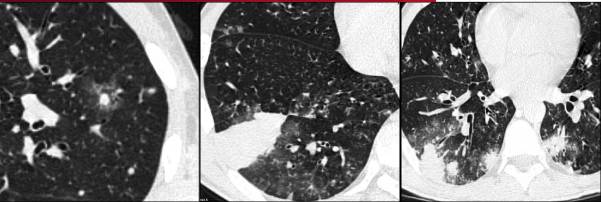

CT表现为大小不一的结节被磨玻璃衰减影(“晕征”)环绕,以胸膜为基底的楔形实变。

晕征是指环绕实性结节或肿块的磨玻璃衰减区。这种表述来自于病理学结果,实性部分代表梗死区域,围绕的磨玻璃边缘来自于肺泡出血。疾病早期,出现晕征的可能性较高,随着时间的推移,可能会逐渐减少。

图2 骨髓移植患者的双侧肺外周实变 “晕征”。血管侵袭性曲霉病